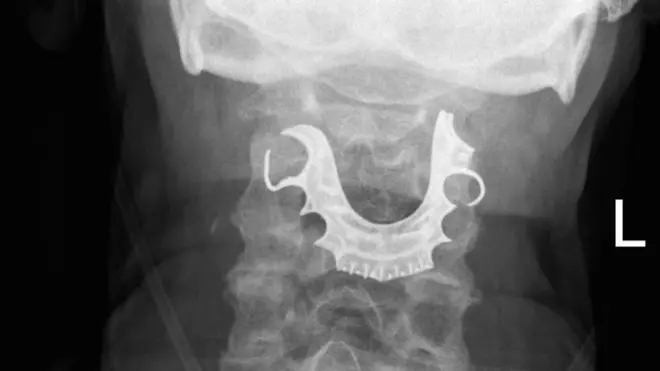

Дијагностификован му је ретки неуролошки поремећај који изазива неконтролисане покрете.

Лекари су одлучили да оперишу, али су Буду замолили да за то време - свира, како би пронашли нервне завршетке и исправили проблем.